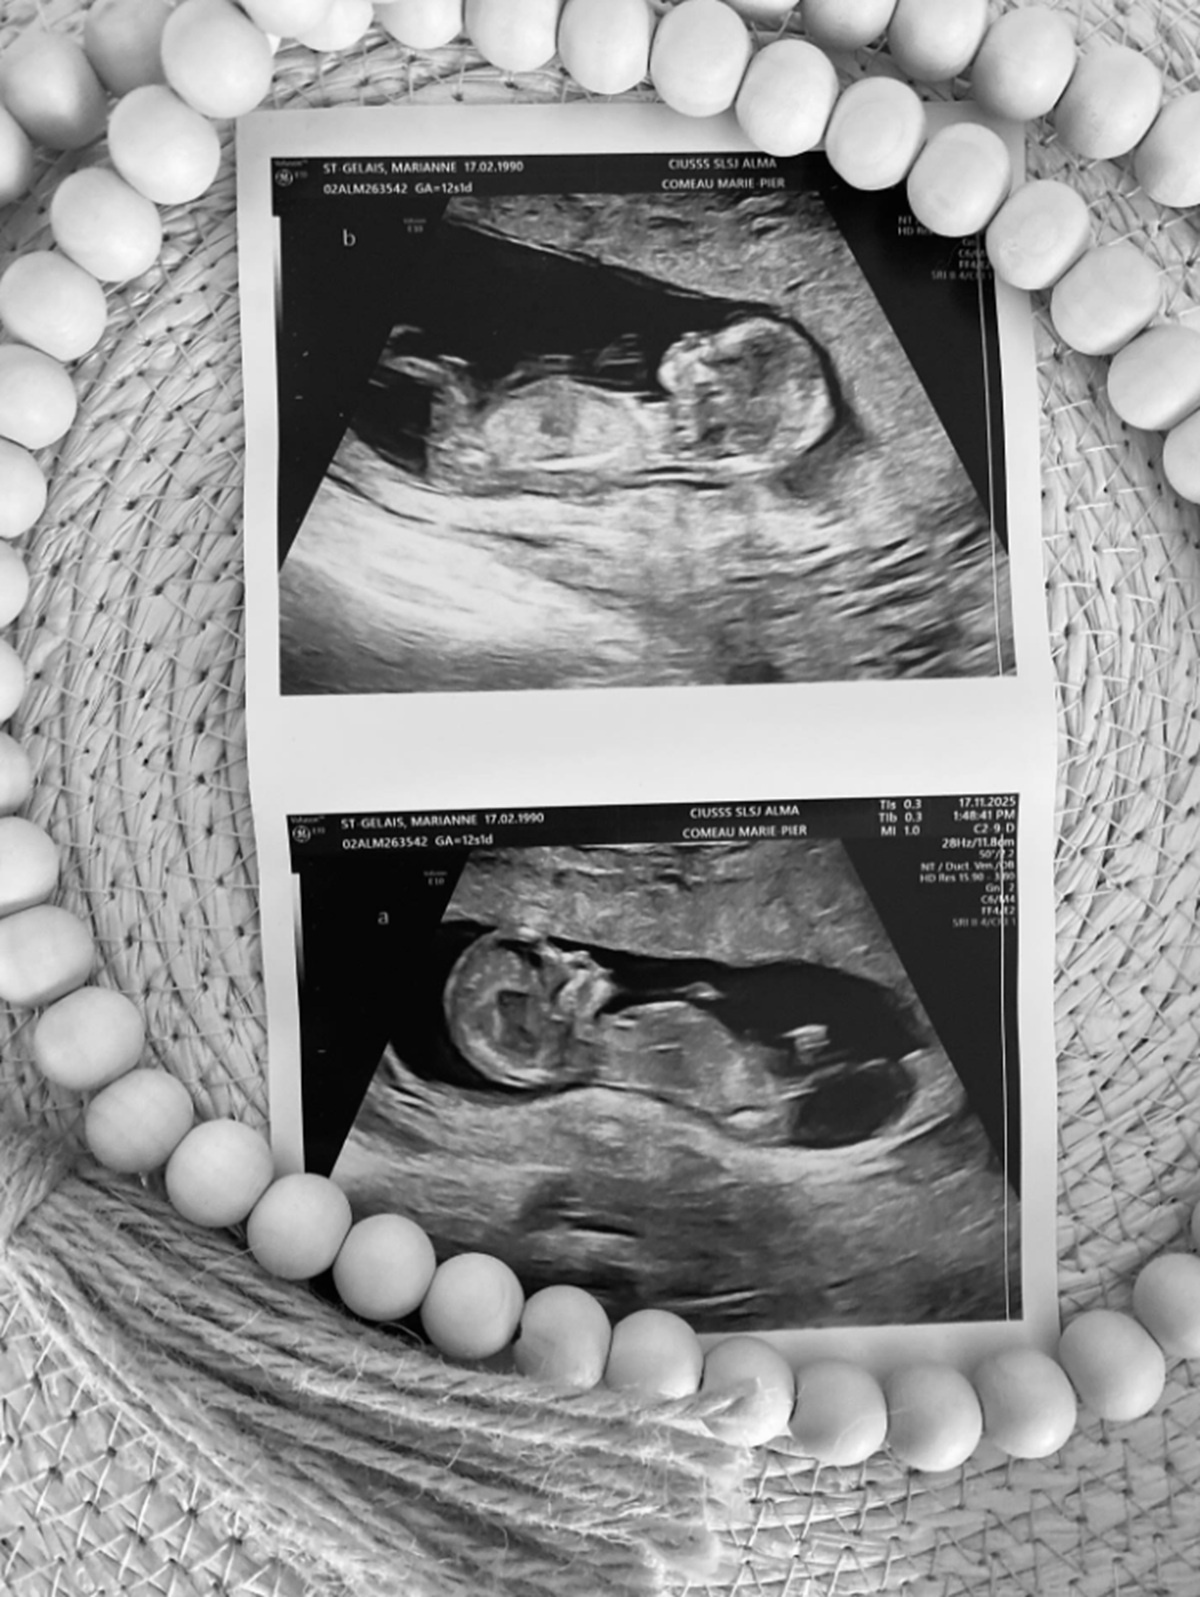

Elle a mis en ligne une publication dans laquelle on apprend qu’elle est présentement enceinte. L’ex-médaillée olympique est en pleine grossesse et elle attend des jumeaux!

Deux beaux trésors viendront compléter notre famille au printemps prochain.